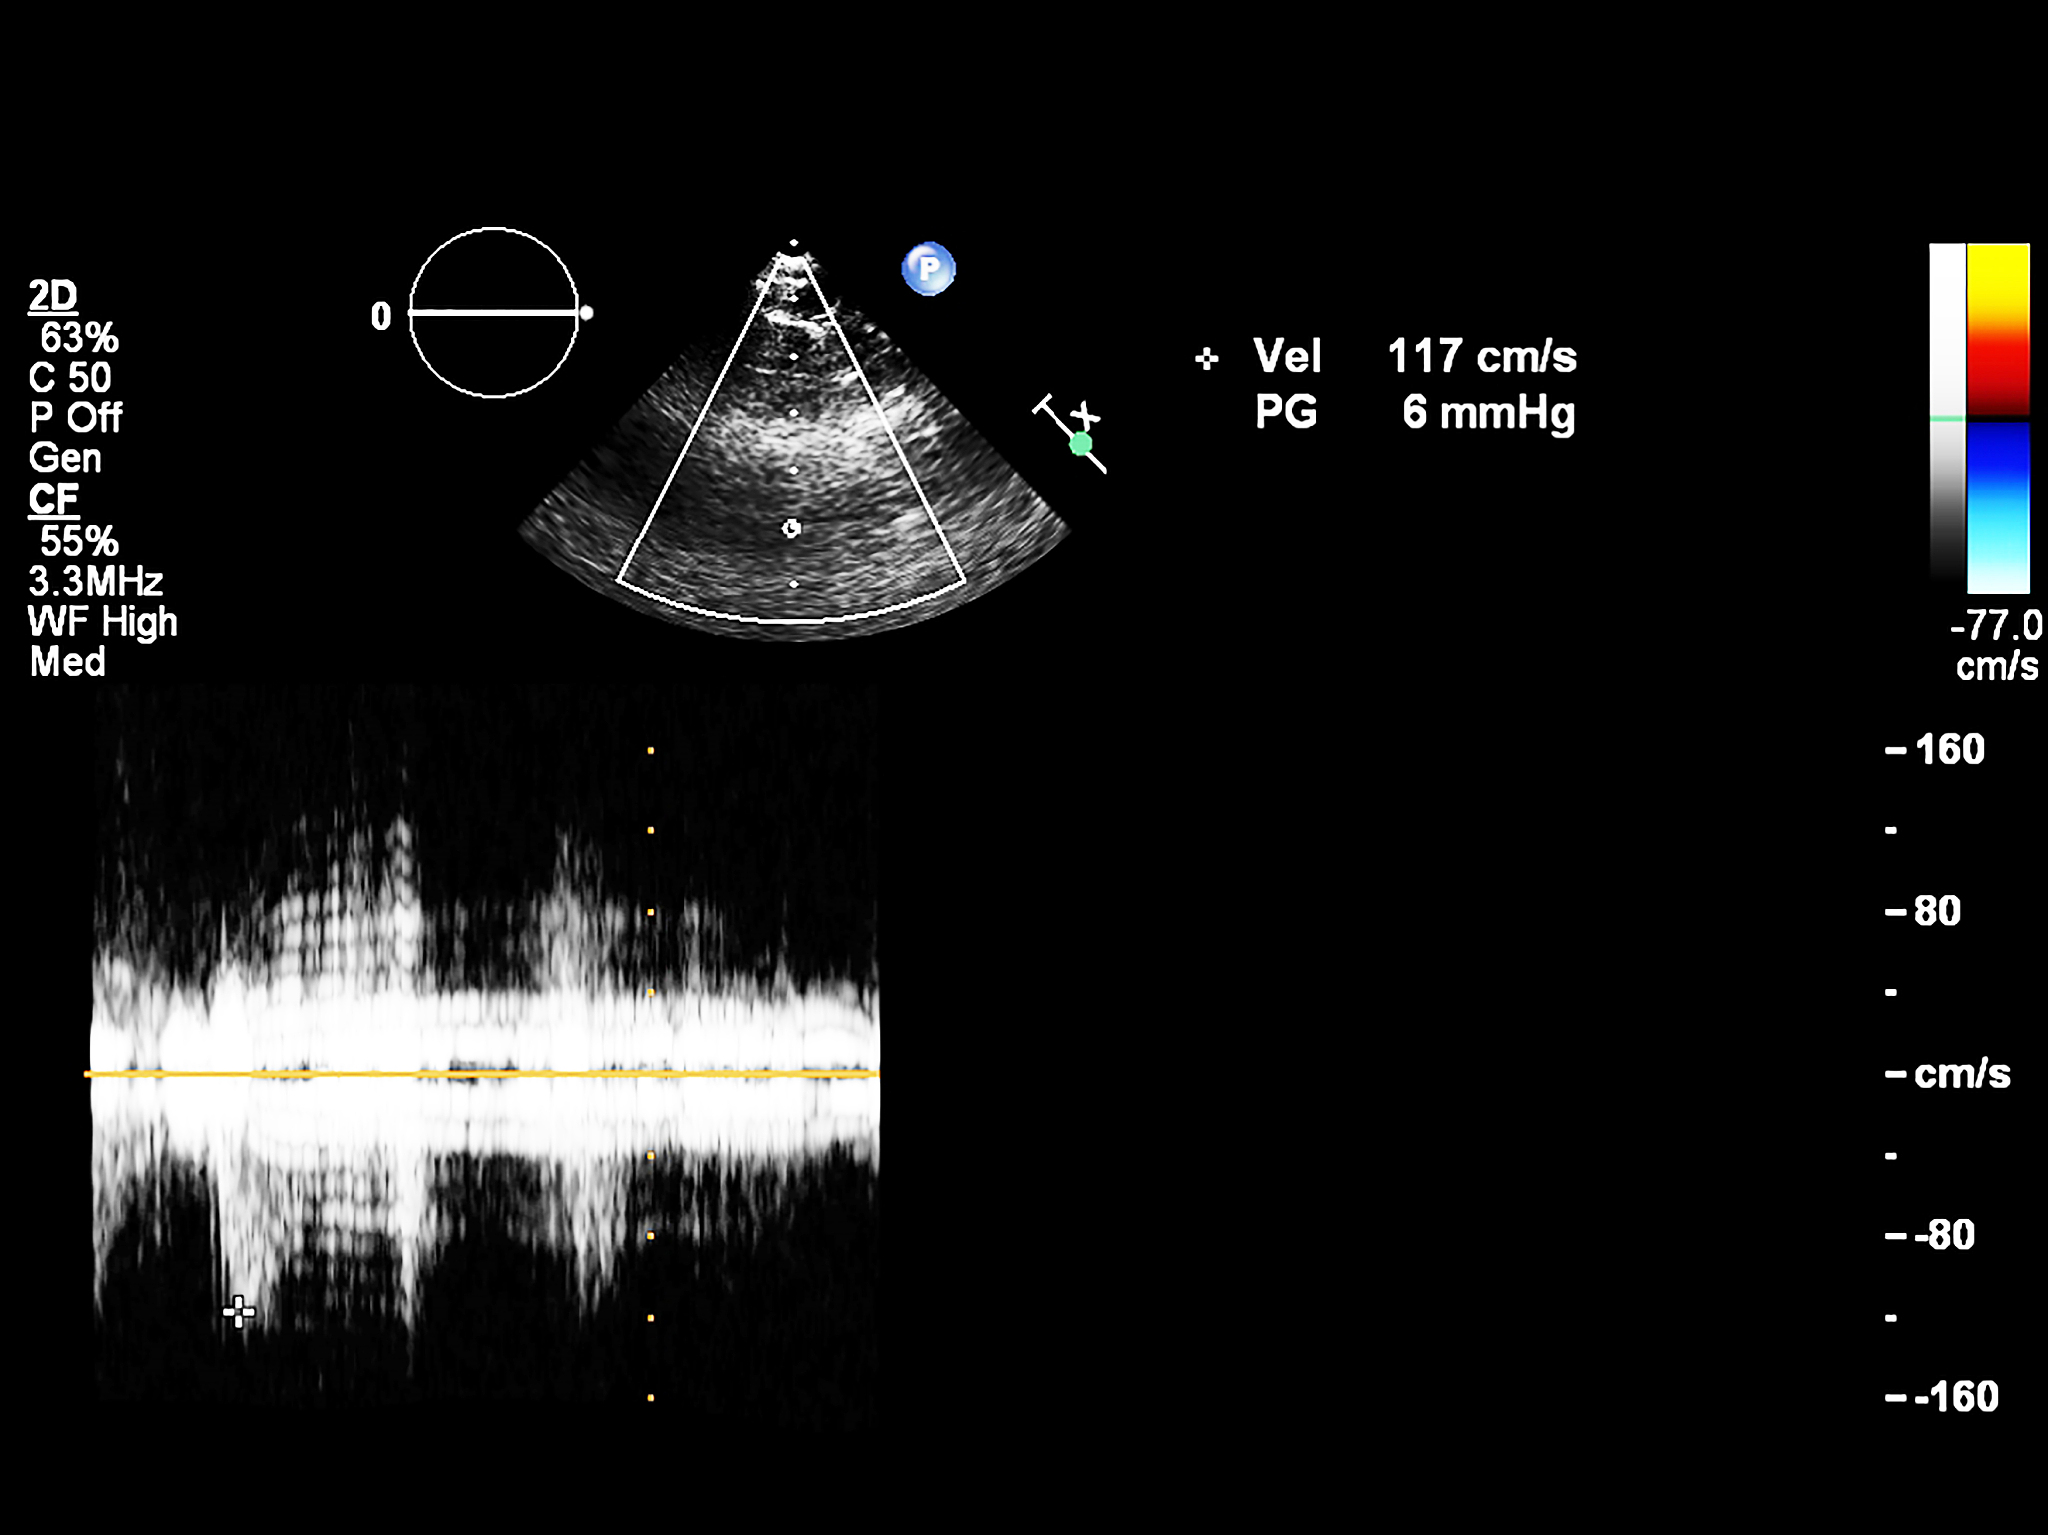

不是的。频率越高,穿透深度越浅。高频超声波的能量更容易被身体组织吸收,因此只能穿透较浅的组织。相反,低频超声波的能量更容易穿透深层组织,但分辨率相对较低。因此,医生会根据需要选择适当的频率,以获得最佳的成像效果。